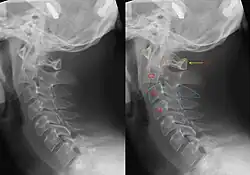

Radiografia da coluna cervical com fratura do pendurado. Esquerda sem, direita com anotação. Pode-se ver claramente que C2 (contorno vermelho) avança em relação a C3 (contorno azul).[5]